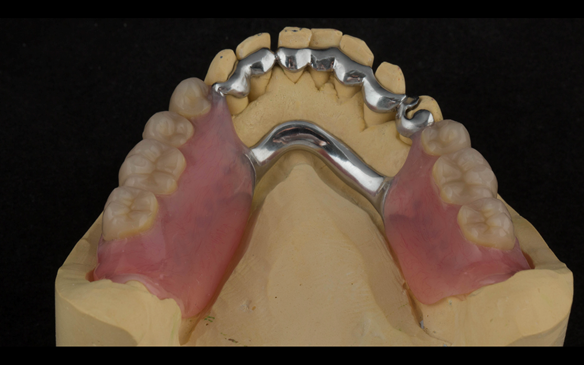

- Definitive dentures (Mk 2) – complete upper metal reinforced and lower cobalt chromium based partial of hygienic Scandinavian design to be made 9 - 12 months after extractions of all upper teeth and LR5 and LL4

The clinical situation and treatment process is shown in detail below with photographs.

The patient has been successfully rehabilitated and is now having periodontal maintenance from Syed Abad, Specialist in Periodontics at the practice. His quality of life has improved considerably. The clinical prosthodontics was provided by me and the technical work by Rowan.